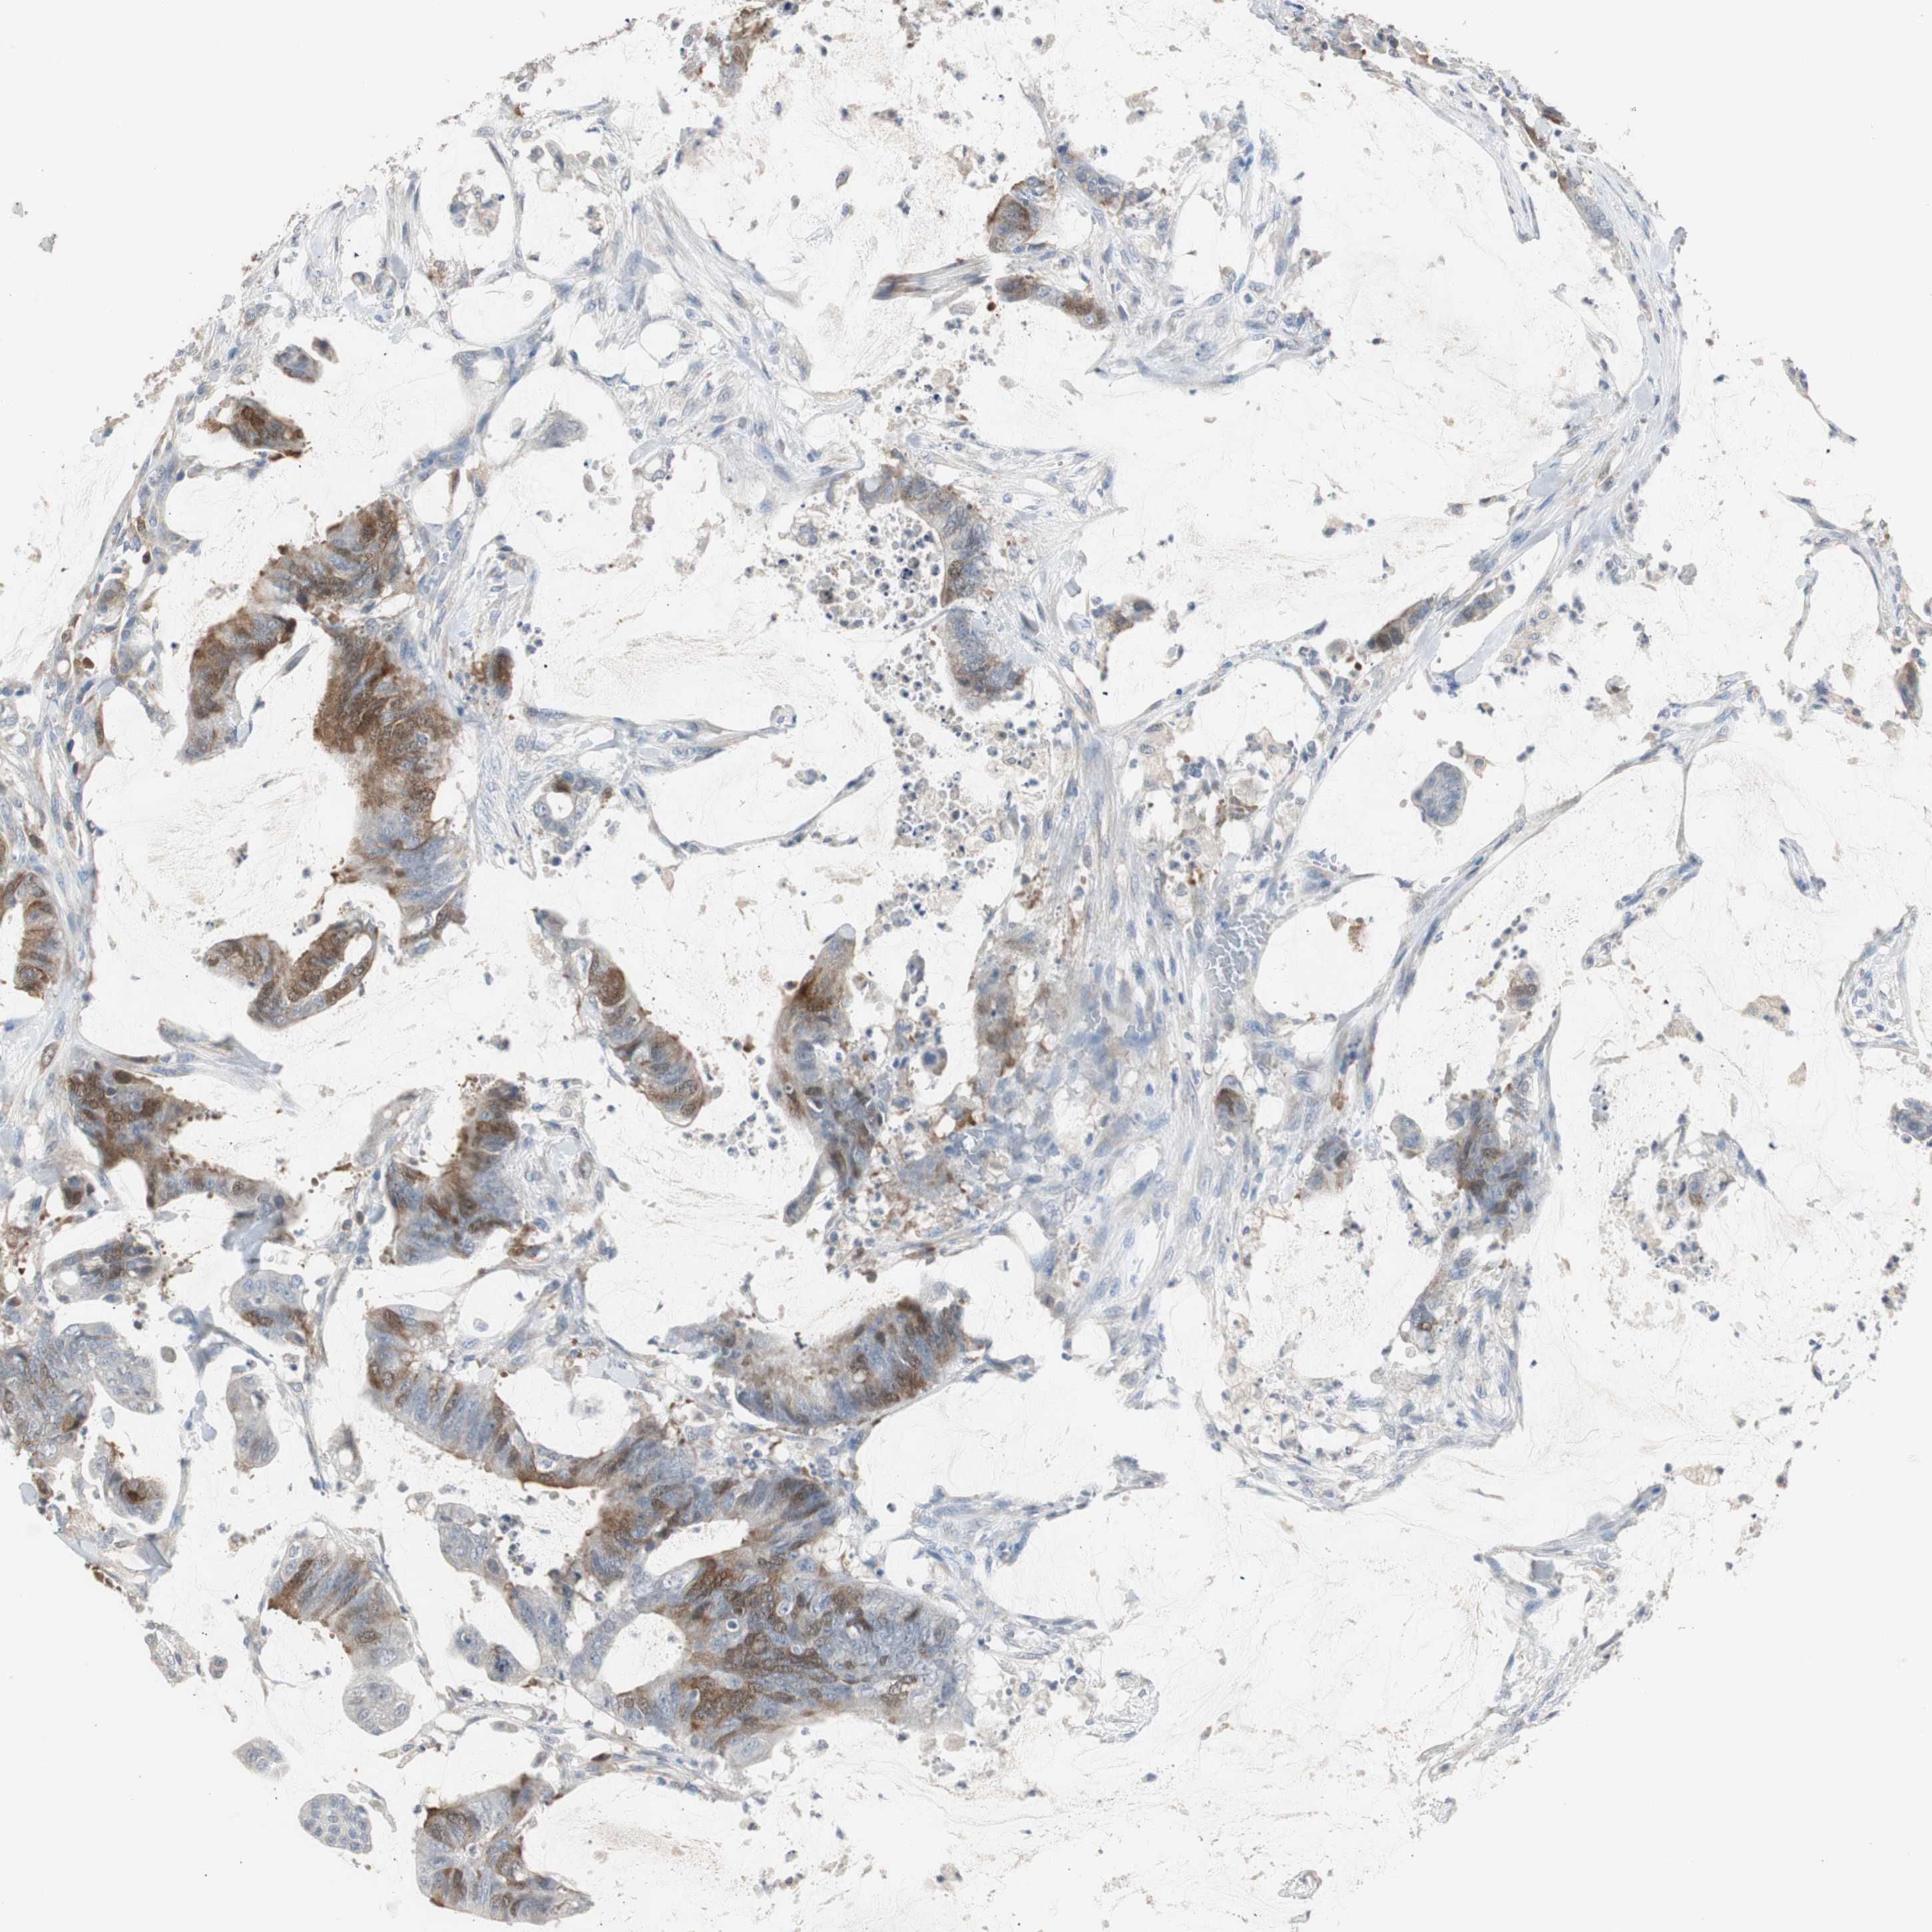

ANTIBODIES

AND

VALIDATION